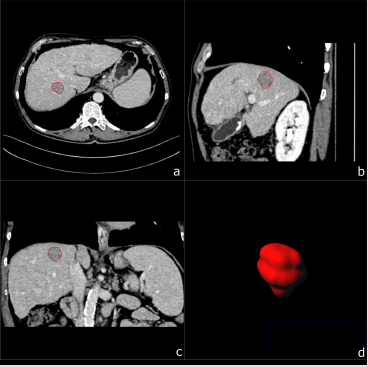

Figure 1: A 67-year-old male patient with biopsy confirmed HCC. Multiplanar image annotation in axial

a) sagittal

b) coronal

c) 3D reformats.

d) of the HCC lesion. From the resulting volume of interest CT textural features are extracted.

One central aspect of this retrospective evaluation of textural features consisted of the possibility to overcome the limitations related to one-phase portal-venous CT-protocols in the differentiation of HCC and CCC (refer to Figure 1 and Figure 2) whilst avoiding unnecessary radiation exposure due to multi-phase protocols required for accurately classifying their enhancement patterns. Our data shows that four of the thirty-five calculated radiomics features derived from the portal-venous enhancement phase proved significant for differentiation of HCC from CCC on a standalone basis. Whereas three of them represent differences in tumor tissue attenuation (1st order Mean, Median and Maximum) one is a measure of local tissue homogeneity (glcm Idmn). All of them yielded significantly higher absolute values for HCC compared to CCC. The use of combinations of features resulted in additional significances. Hence, the use of a combination of two textural features like 1st order Maximum and grey-level dependency matrix dependence non-uniformity or neighboring grey-tone difference matrix (ngtdm) contrast resulted in a slight increase in sensitivity, but also a slight decrease in specificity. The same was observed for the gray-level co-occurrence matrix (glcm) combined with the gray level run length matrix run entropy.